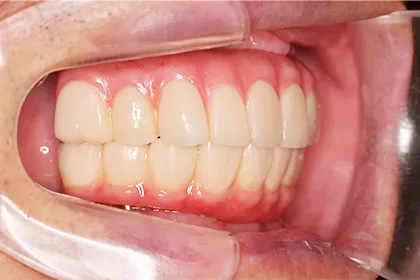

インプラント症例▼クリックして開閉できます

- AFTER

| 年代・性別 | 70代・男性 |

|---|---|

| 主訴 | 今使っている入れ歯が合わず、嚙むと痛い |

| 治療部位 | 15~26、36、45 |

| 治療内容 | 上下顎インプラント埋入術(上顎5本、下顎2本)を、2回に分けて実施。26部はソケットリフトを適用し、2回法で実施。他部位は1回法。 |

| 金額(税込) | 29,000,000円(税込) |

| 治療期間 | 7カ月(インプラント埋入から上部構造装着まで) 12年経過例(2024年3月時点) |

| リスクと副作用 | 手術部位の腫脹、疼痛 マスダ歯科のインプラント詳細はこちら |